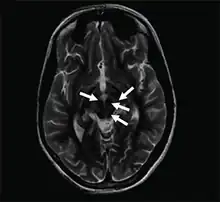

| Axial T2-weighted MRI of the brain at the level of the midbrain showing the characteristic ‘face of the giant panda’ sign, with normal red nuclei and substantia nigra (pars reticulata) against a background of hyperintensity in the tegmentum, as well as hypointensity of the superior colliculi | |

The face of the giant panda sign, panda sign of the midbrain or double-panda sign is a characteristic "panda's face" appearance in magnetic resonance imaging (MRI) images of people with Wilson's disease. Along with Kayser–Fleischer rings, the sign is helpful in diagnosis.[1]